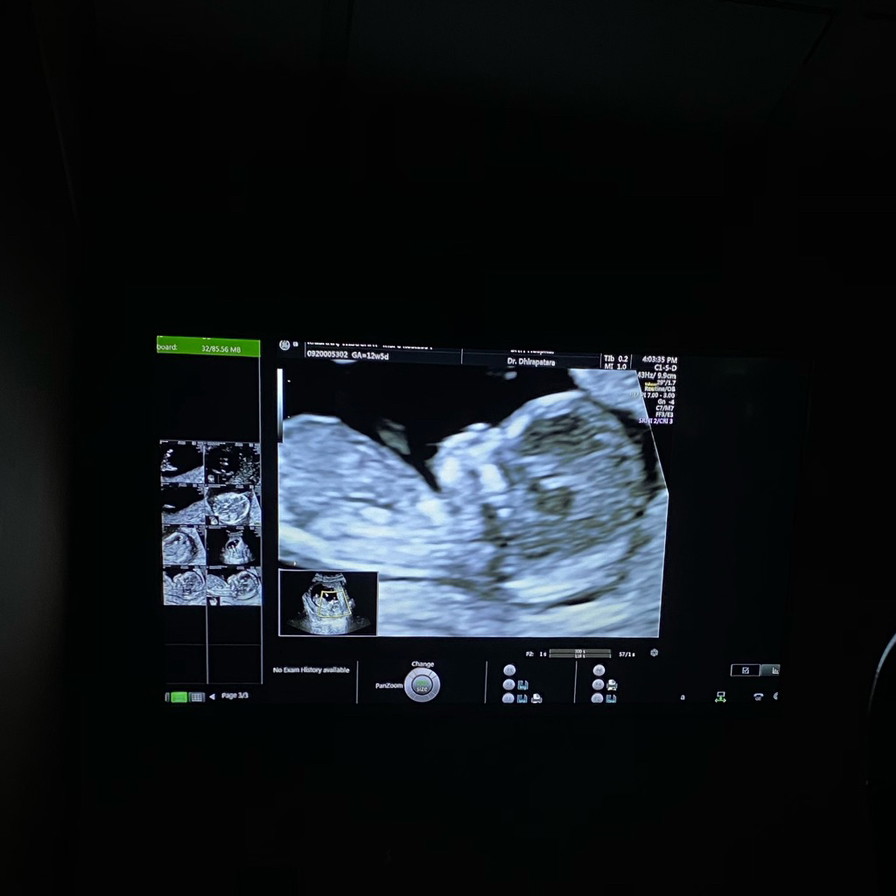

12w5 d ค่ะ